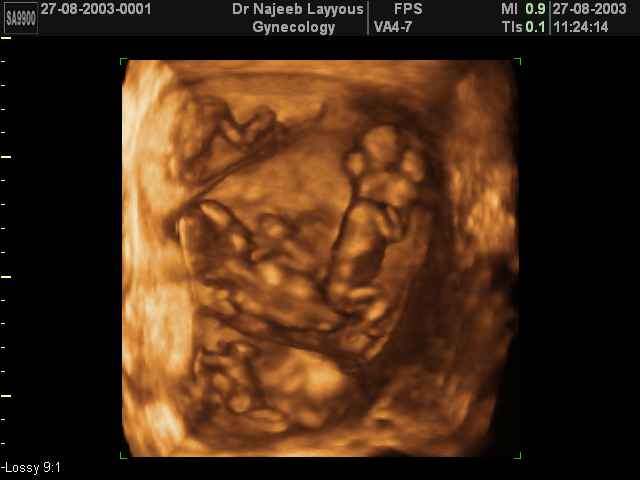

هي حامل صار لها شهرين واسبوعين .. يعني بالثالث ...عملت سونار في نهايه الشهر الثاني وقالت الدكتوره انه كيس واحد وجنين واحد .. لكن قالت فيه اكياس على المبيض اليسار وانها طبيعيه واحتمال تختفي في الشهر الثالث اوالرابع او نهايه الحمل او حتى انها يمكن ماتختفي ومامنها اي ضرر ان شاء الله وانها طبيعي تصير ....

السؤال هو .. هل ممكن تكون الأكياس كيس حمل ثاني .. يعني فيه توأم ومابين في نهايه الشهر الثاني ؟؟؟؟

اجنة خماسية كوينتبلتز